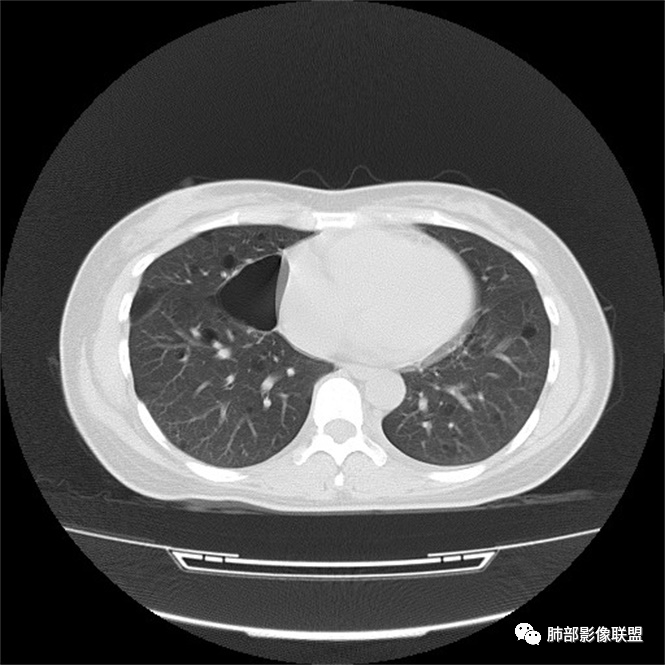

秦化君: 晨读 双肺不均匀散在多发囊状影,大小不等,部分囊形态欠规整,壁薄均匀,部分囊胸膜下平行。双肺少许斑片状磨玻璃影,边缘模糊。考虑BHD综合征。鉴别PCP,LIP。

红日初升: 中年女性,双肺多发气囊,背景干净,大小不一,下肺韧带旁较大,考虑BHD,鉴别LIP、LAM

玫: 晨读:女,49岁,双肺散在多发囊性病灶影,薄壁,部分层面病灶形态欠规整,右肺下叶少许磨玻璃影,边缘模糊,考虑LIP,鉴别BHD。

宇宙: 中年女性,两肺多发大小不等薄壁囊状影,两肺纵膈胸膜下分布明显,考虑BHD,鉴别LAM

放射线 (王秀仙): 双肺多发囊状影,大小不等,部分囊壁呈磨玻璃样,另双肺见斑片状磨玻璃影,边缘模糊。女性,考虑LIP,鉴别BHD

段建民: 双肺多发囊状影,多成圆形或三角形,囊壁薄且均匀,正常肺野内透过度尚可。双肺多发囊状影的鉴别,中心肺气肿,间隔旁肺气肿,PJP,支气管扩张,囊肿,支气管肺发育异常;LAM LIP PLCH BHD;囊腔腺癌,转移瘤,血播金葡菌……

本病例首先考虑BHD。

良孑: 两肺多发含气囊腔,大小不等,囊周见血管伴行,首选BHD,建议查双肾情况,鉴别Lam

这个病例目前影像特点,多囊,囊主要位于下肺,胸膜下及小叶核心为主

伴随少许索条,而且这些病灶与囊不一定有相关性

囊的分布,PLCH基本可以排除

囊壁薄且均匀,光滑,形态规则,基本除外恶性

单纯囊,无斑片及其他实性病灶,感染不支持,可能的是:LAM、BHD、LIP

从囊的分布、大小,BHD可能性可能大一些,但是LIP、LAM都可以这样表现,具体诊断应该是这三种之一,影像缩小到这里我觉得就差不多了,结合临床考虑就行,不支持靠影像强下结论。

临床诊断BHD综合征需要满足一个主要或两个次要标准。主要标准包括:1、皮肤上至少发现5个纤维滤泡瘤,至少1个组织学证实;2、致病的FLCN种系突变阳性。次要标准:1、多发肺囊肿,双侧基底部,有或无自发性气胸;2、肾癌,起病早(<50岁)或多灶性或双侧;3、 BHD综合征一级亲属。BHD主要影像表现特征:1、两肺内肺囊肿:80%以上的BHD患者会出现肺内囊肿,且倾向于基底部近胸膜下分布,特别是纵隔侧肺膜下,囊肿形状不规则、囊肿可大可小,肺内囊肿多毗邻肺下动脉或静脉近端,胸部CT上囊肿分布和特点对诊断有提示意义。2、继发自发性气胸:BHD患者发生气胸风险是正常人的5倍,BHD患者的气胸发生率约为1/4,气胸复发率则高达59%。3、肾肿瘤:(常为双侧性、倾向于嫌色细胞组织学亚型)4、皮肤表现:(为面、颈部纤维性毛囊瘤、毛盘瘤)